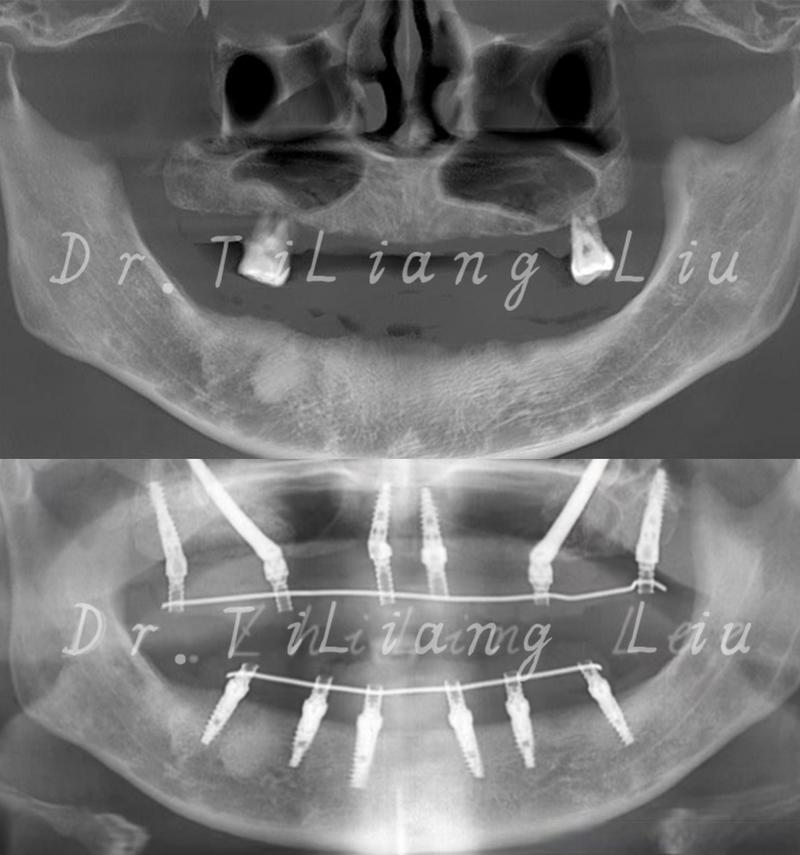

针对骨量不足靠近上颌窦的情况,种植牙医生通常不会直接种植,而是会采用以下上颌窦提升术来增加骨量,确保种植体安全植入:

上颌窦提升术(也叫上颌窦底增高术)

这是解决上颌窦区域骨量不足的标准方法,其原理是通过外科手术,将上颌窦底壁的骨膜和黏膜(称为“上颌窦粘膜”)向上推起,在窦底和推起的粘膜之间创造一个空间,然后填入骨移植材料,诱导新骨形成,从而增加骨高度。

外提升术(开放式):

- 适用情况: 骨量严重不足(通常剩余骨高度<4-5mm),或者需要同时提升较大范围。

- 手术过程: 在缺牙位置的牙槽嵴顶做一个小切口,翻开牙龈骨膜瓣,暴露上颌窦前外侧壁,在窦底开一个“窗”,小心地将上颌窦粘膜完整剥离并向上推起,将骨移植材料(自体骨、异体骨、人工骨或混合物)填入剥离出的空间,将骨膜瓣复位缝合。

- 特点: 视野清晰,提升高度大,但创伤相对较大,术后反应(肿胀、不适)可能稍重,通常需要4-6个月的骨愈合期,之后才能植入种植体(有时也可在提升时同期植入,称为“同期种植”,但要求条件更严格)。

内提升术(闭合式/经牙槽嵴顶):

- 适用情况: 剩余骨高度中等(通常5-10mm),骨质量尚可。

- 手术过程: 不需要切开上颌窦外壁,在缺牙位置的牙槽嵴顶做一个小切口,用特制的骨凿或超声骨刀,在窦底骨板上小心地敲击或抬起,将上颌窦粘膜整体向上推起,将骨移植材料填入抬升的空间,缝合伤口。

- 特点: 创伤小,手术时间短,术后反应轻,通常也需要4-6个月的骨愈合期,有时也可同期植入种植体(称为“同期种植”),但需严格评估骨支撑和初期稳定性。